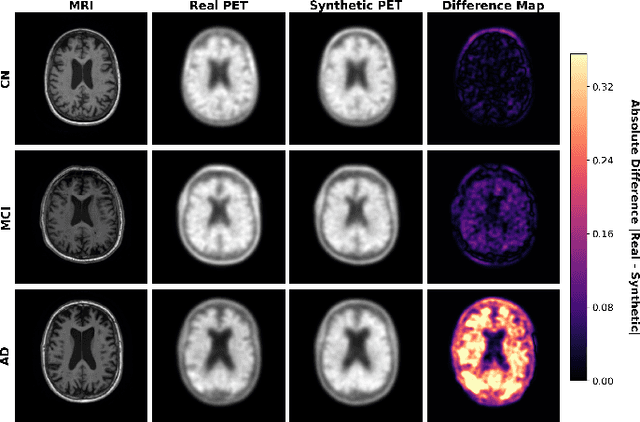

Abstract:Beta-amyloid positron emission tomography (A$\beta$-PET) imaging has become a critical tool in Alzheimer's disease (AD) research and diagnosis, providing insights into the pathological accumulation of amyloid plaques, one of the hallmarks of AD. However, the high cost, limited availability, and exposure to radioactivity restrict the widespread use of A$\beta$-PET imaging, leading to a scarcity of comprehensive datasets. Previous studies have suggested that structural magnetic resonance imaging (MRI), which is more readily available, may serve as a viable alternative for synthesizing A$\beta$-PET images. In this study, we propose an approach to utilize 3D diffusion models to synthesize A$\beta$-PET images from T1-weighted MRI scans, aiming to overcome the limitations associated with direct PET imaging. Our method generates high-quality A$\beta$-PET images for cognitive normal cases, although it is less effective for mild cognitive impairment (MCI) patients due to the variability in A$\beta$ deposition patterns among subjects. Our preliminary results suggest that incorporating additional data, such as a larger sample of MCI cases and multi-modality information including clinical and demographic details, cognitive and functional assessments, and longitudinal data, may be necessary to improve A$\beta$-PET image synthesis for MCI patients.